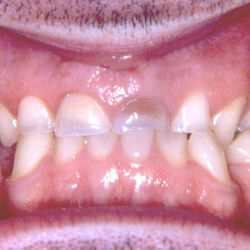

Ο 43χρονος αυτός ασθενής προσήλθε στο ιατρείο μας με έντονες αποτριβές των προσθίων και οπισθίων δοντιών του.

Ο αιτιολογικός παράγοντας για την καταστροφή της οδοντικής του ουσίας ήταν τα γαστρικά οξέα λόγω της χρόνιας γαστρο-οισοφαγικής παλινδρόμησης που παρουσίαζε.

Τα πρόσθια δόντια του αποκαταστάθηκαν με χτίσιμο σύνθετης ρητίνης επί τόπου ενώ τα οπίσθια δόντια του αποκαταστάσθηκαν με εργαστηριακά κατασκευασμένα επένθετα σύνθετης ρητίνης